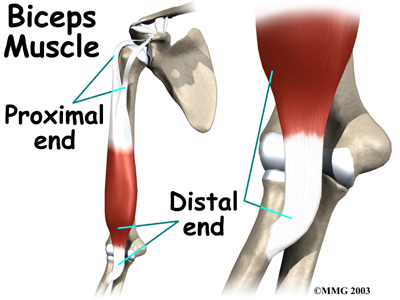

The biceps muscle goes from the shoulder to the elbow on the front of the upper arm. Tendons attach muscles to bone. Two separate tendons connect the upper part of the biceps muscle to the shoulder. One tendon connects the lower end of the biceps to the elbow.

The lower biceps tendon is called the distal biceps tendon. The word distal means that the tendon is further down the arm. The upper two tendons of the biceps are called the proximal biceps tendons, because they are closer to the top of the arm.

The upper (proximal) end of the biceps has to the shoulder. The main attachment is the long head of the biceps. It connects the biceps muscle to the top of the shoulder socket, called the glenoid. The short head of the biceps angles up and in to its attachment on the corocoid process of the shoulder blade. The corocoid process is a small bony knob in the front of the shoulder.